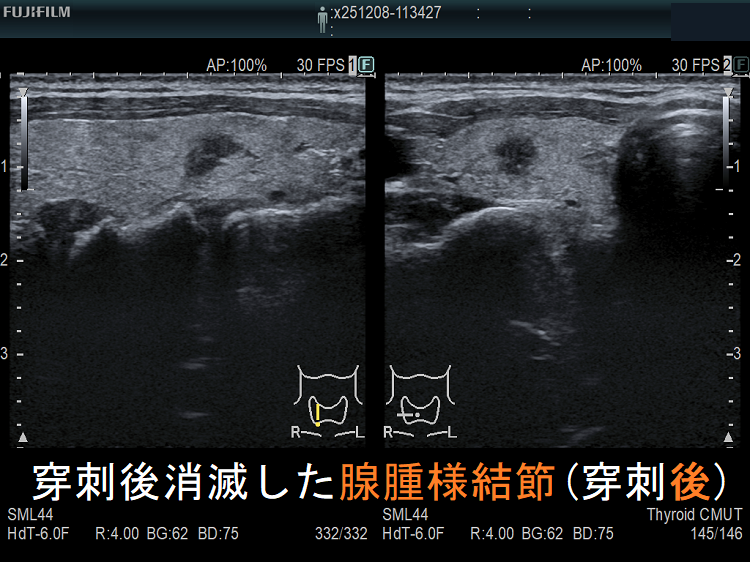

穿刺細胞診後内部融解

ケース①

ケース②